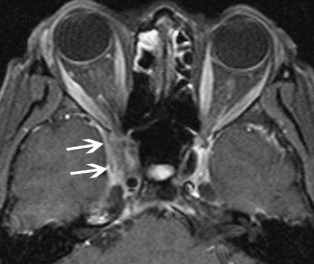

Orbital apex, cavernous sinus, and intracranial involvement

There may be compression or displacement of the optic nerve. The cavernous sinus (Figure 7) and middle cranial fossa are the 2 most common locations for intracranial extension of NSOI. Intracranial involvement can feature abnormal soft tissue in the superior orbital fissure, expansion of the ipsilateral cavernous sinus, and thickening of the meninges contiguous with the orbital inflammation.

Figure 7: MRI, fat-saturated, T1-weighted image with white arrows showing extension into the cavernous sinus. (Courtesy of Z.X. Ding).